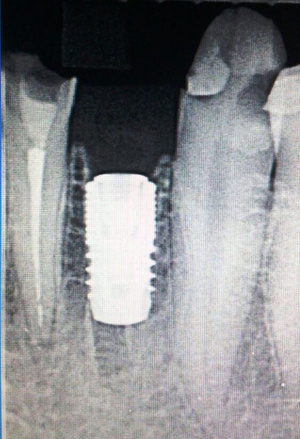

Удаление+ имплантация.

Фронт. Удаление + Конмет(Россия).

Бок. отдел. Удаление+Implant Direct (USA).

Левый крайний диаметр 7.0 мм,для использования одномоментно в лунку моляра.